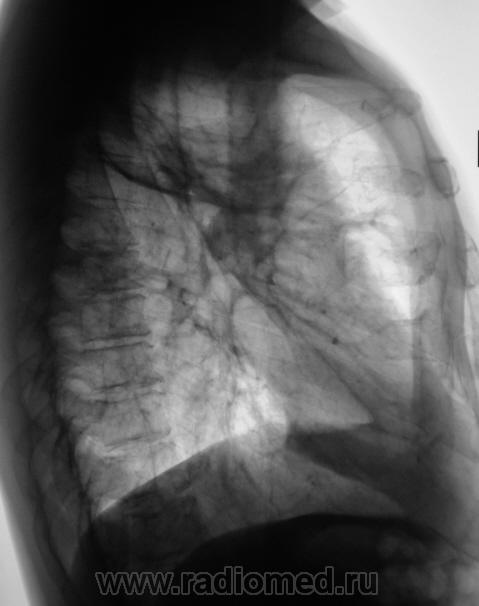

Произведено дообследование.

ИзображениеИзображениеИзображение

Пациент направлен на консультацию к фтизиатру. Произведено общеклиническое дообследование, пациент госпитализирован в туб. большицу.